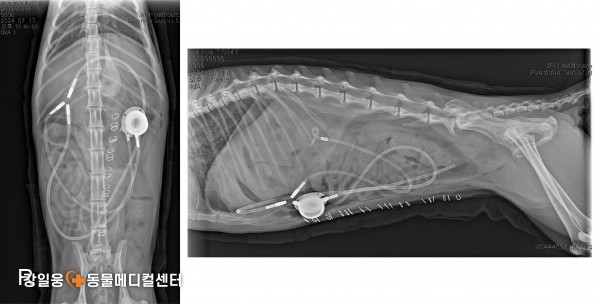

고양이 요관 폐쇄, SUB 수술로 새로운 길을 열다

SUB 수술(Subcutaneous Ureteral Bypass)

SUB 수술(Subcutaneous Ureteral Bypass) 은

요관이 막혔을 때 신장에서 방광으로 새로운 우회로

(인공 튜브)를 만들어 소변이 원활히 배출되도록 돕는 수술입니다.

쉽게 말해, 막힌 도로(요관)

대신 새로운 길을 만들어

신장에 고여 있던 소변이 다시 정상적으로

방광으로 내려가게 하는 수술입니다.

강일웅동물메디컬센터 정형·신경외과 전승하 원장은

그동안 다양한 원인으로 요관이 막힌 고양이들을 치료하며

여러 형태의 SUB 수술 사례들을 해결해 왔습니다.